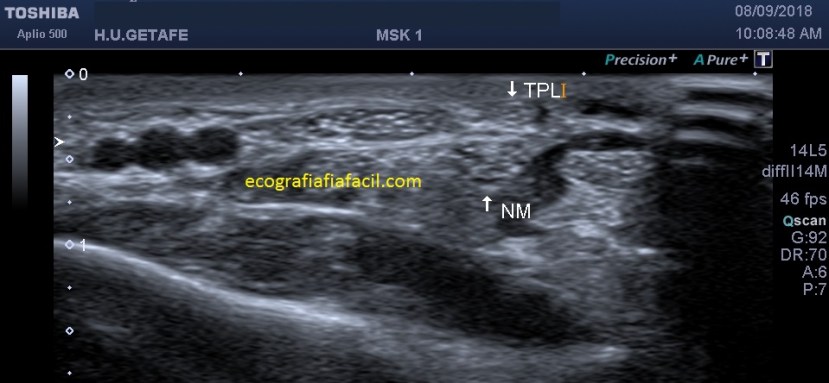

En la imagen siguiente, ejemplo típico de de calcificaciones con Entesitis de la inserción. Se observa una imagen lineal hiperecogénica en la inserción del tendón con hipoecogenicidad local…

Ahora el corte transversal…